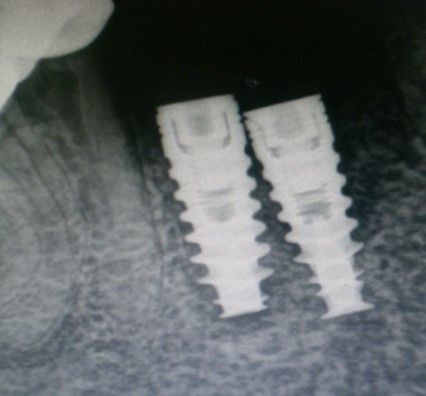

Unplanned implant placement or change in angulations of the implants due to anatomic limitations3,4 such as mandibular canal, mental foramen, nasal floor, sinus cavities or roots of the adjacent teeth, might result in close approximation of the implants (Figure 1), which poses tough challenges to the restorative dentist, who have to overcome certain technical difficulties for the fabrication of the prosthesis including making of a proper impression.

Figure 1.Radiograph – closely positioned implants.